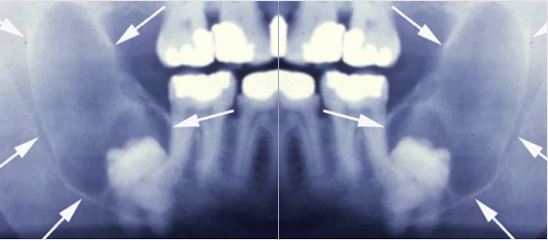

Các nang (vùng mũi tên) có thể phát triển từ biểu mô xung quanh răng khôn mọc ngầm. Nang gây nên hiện tượng phá hủy xương hàm, vùng phá hủy rộng gây xô đẩy và tổn thương các răng bên cạnh. Phẫu thuật loại bỏ răng khôn và bóc tách nang là rất cần thiết để ngăn chặn hiện tượng tiêu xương.

Mộ số trường hợp hiếm gắp khối u gấy ra do răng khôn mọc ngầm có thể gây gẫy xương tự phái nếu kích thước khối u lớn.